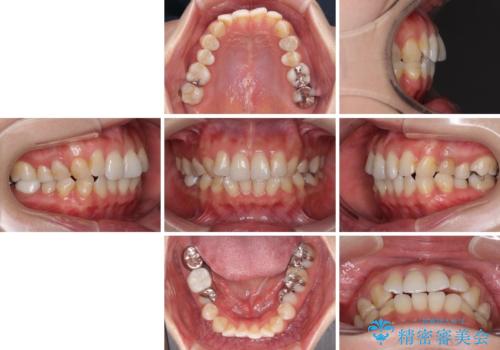

- 失活により変色した歯と不揃いな口元を気にして来院された患者様です。

口元をインビザラインにより歯列を整え、その後に失活している奥歯をオールセラミッククラウンにて補綴治療することとしました。

長時間のマウスピース装着と、患者様自身でのゴムかけに協力いただき、自然な口元に仕上げることができました。

気になっていた変色した歯もオールセラミッククラウンで本物の歯のようになり、患者様には大変満足していただきました。